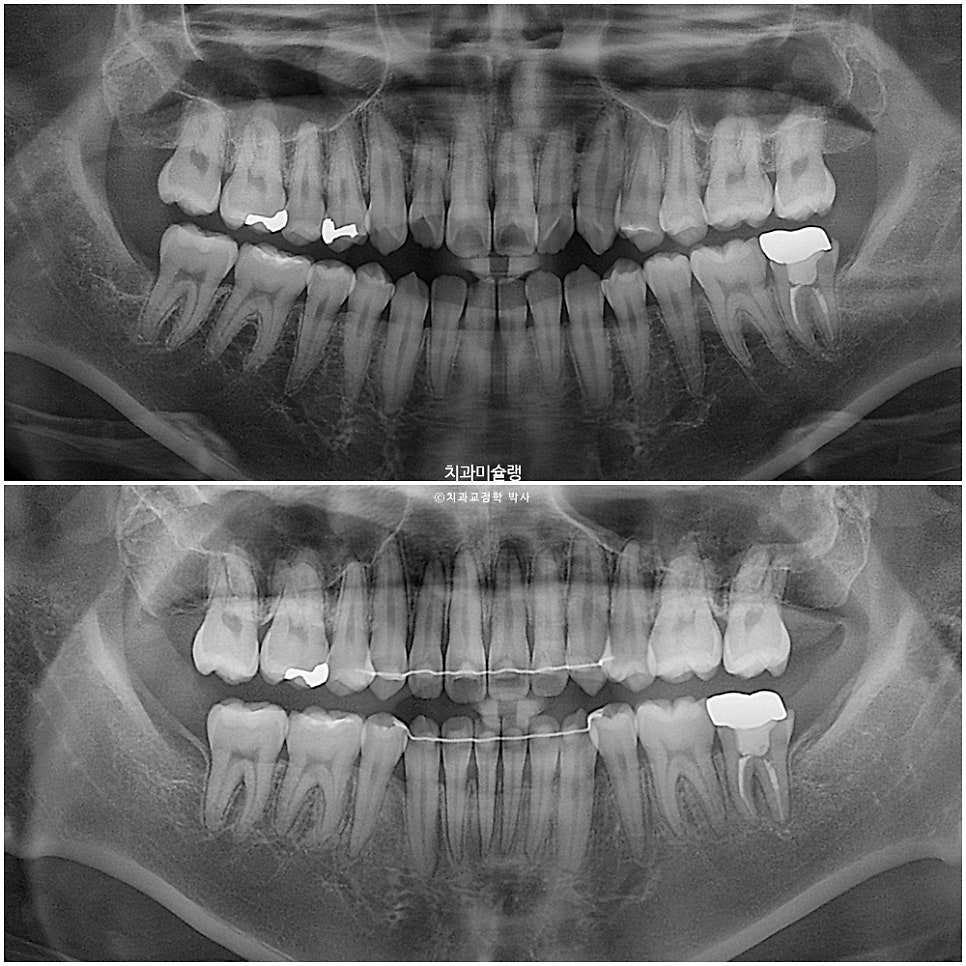

엑스레이 비교

1년 11개월의 변화를 엑스레이로 보면 이러합니다.

교정기간동안 치근흡수는 없으며 치근 평행도는 양호합니다.